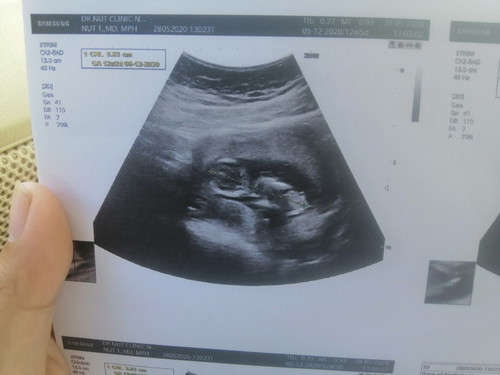

22ธ.ค.จ้าา อันนี้ซาวตอน10w3d เมื่อวันที่1มิ.ยค่ะ